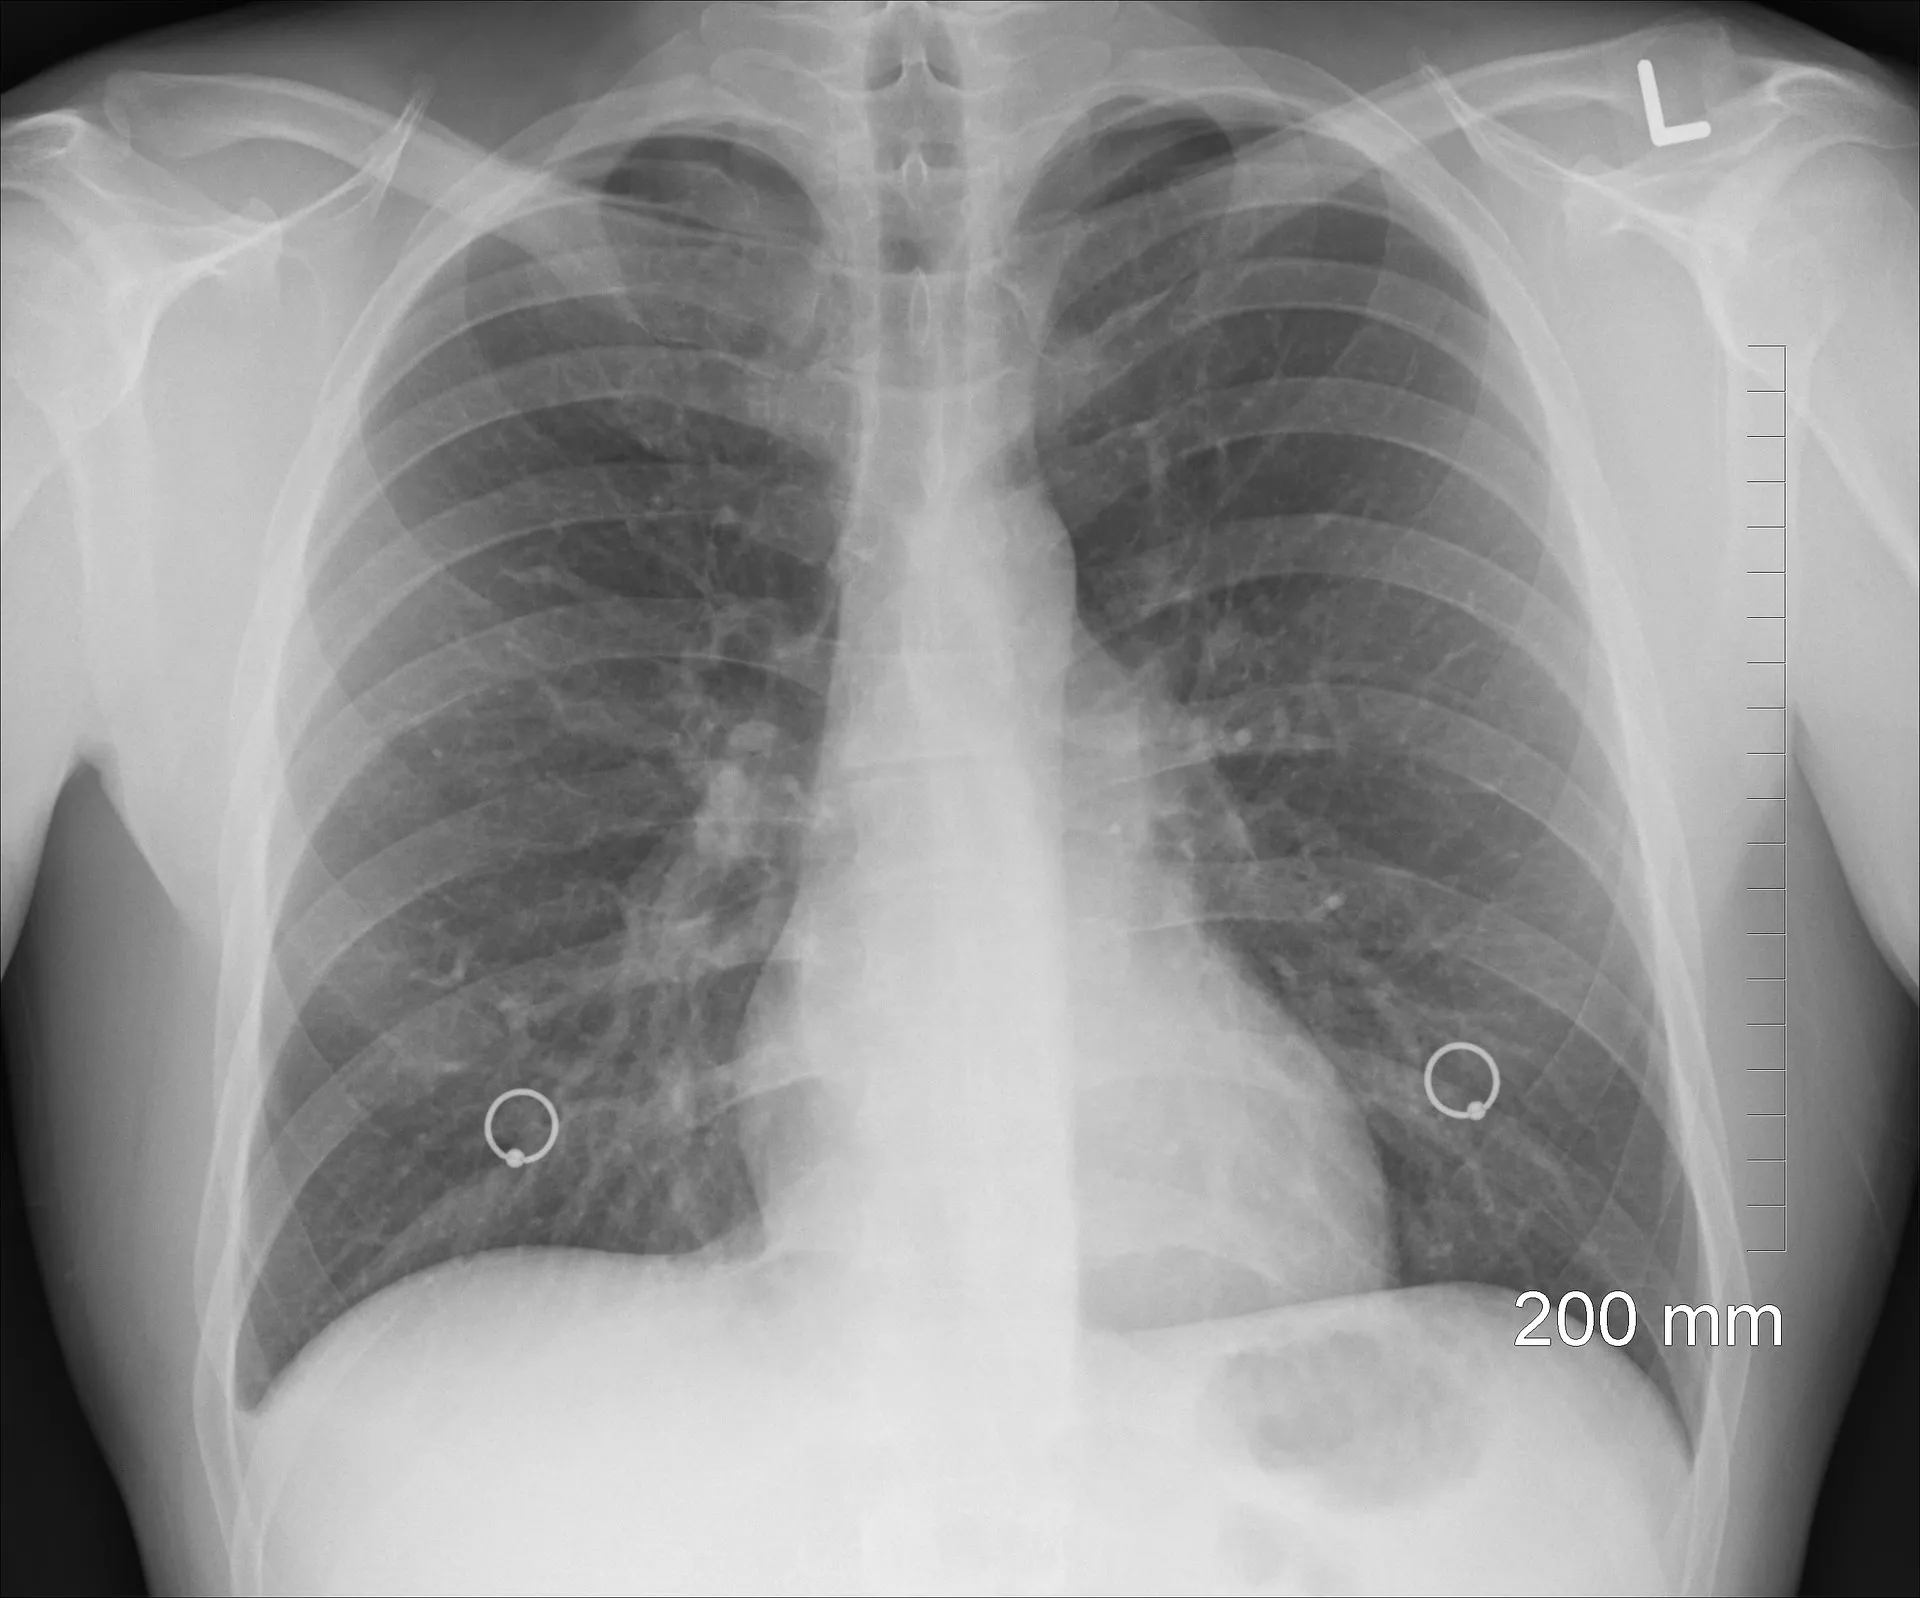

Il riscontro di un nodo polmonare è il più delle volte casuale e spesso la sua scoperta avviene, in pazienti assolutamente asintomatici, in occasione di un esame radiografico del torace praticato per motivi indipendenti dalla sua presenza (esami richiesti in previsione di un intervento chirurgico, assunzione al lavoro, trauma del torace, ecc). La presenza di bolle d'aria circolanti nel sistema vascolare può essere assai pericolosa, in quanto gli emboli potrebbero raggiungere anche le arterie del cervello, le coronarie che irrorano il muscolo cardiaco e i vasi sanguigni che conducono il sangue deossigenato dal cuore ai polmoni Se le bolle d'aria finiscono nei vasi arteriosi del. L’aria entra nel corpo attraverso il naso o la bocca, passa attraverso la trachea e i bronchi per giungere quindi ai polmoni Quando inspiriamo, i polmoni si espandono con l’aria ed in questo modo il corpo riceve l’ossigeno, mentre quando espiriamo l’aria esce da questi organi ed il corpo si libera dell’anidride carbonica.

L’ enfisema polmonare è un malattia dei polmoni provocata da un danneggiamento degli alveoli in essi contenuti La causa più comune risiede nell’inalazione di sostanze dannose contenute per esempio nel fumo di sigaretta, nell’aria inquinata o nelle esalazioni di certi impianti industriali. Il riscontro di un nodo polmonare è il più delle volte casuale e spesso la sua scoperta avviene, in pazienti assolutamente asintomatici, in occasione di un esame radiografico del torace praticato per motivi indipendenti dalla sua presenza (esami richiesti in previsione di un intervento chirurgico, assunzione al lavoro, trauma del torace, ecc). Formazione di bolle giganti nei polmoni le bolle sono spazi che nascono all'interno del polmone, responsabili di una riduzione della capacità respiratoria;.

Struttura sferica anomala, piena d’aria, che si sviluppa all’interno del polmoneSi forma nel tessuto polmonare anormale, disteso, talvolta distrutto, e non è funzionale, non assicura cioè gli scambi gassosi tra sangue e aria Le sue dimensioni vanno da meno di 1 cm alla grandezza dell’intero polmoneLe bolle possono comparire nel polmone sano o malato, colpito da enfisema. Infine si può optare anche per l’intervento chirurgico, che consiste nell’asportare la zona di polmone occupata dalle bolle d’aria, in genere molto piccola, la cui rottura ha causato la. Le bolle polmonari sono strutture sferiche piene d'aria, di varie dimensioni, singole o multiple, che si sviluppano anormalmente all'interno del polmone Possono essere congenite, cioè presenti.

Le bolle impediscono al polmone di espandersi e di spostare l’aria dentro e fuori;. Piccole bolle d’aria possono svilupparsi sulla parte superiore del polmone Non si sa perché queste vesciche appaiano sui polmoni di alcune persone e non di altre, ma si verificano più spesso in persone che sono alte e magre. Formazione di bolle giganti nei polmoni le bolle sono spazi che nascono all'interno del polmone, responsabili di una riduzione della capacità respiratoria;.